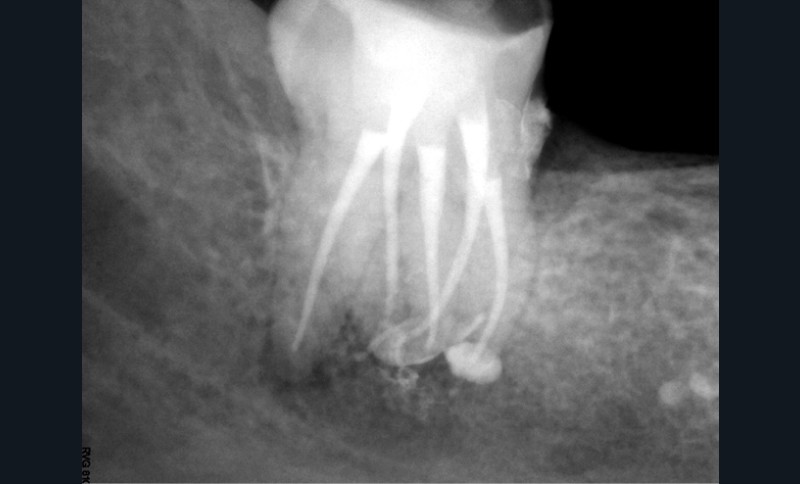

Endal, en 2011, montrait également, en utilisant le micro CT Scanner, l’insuffisance de nettoyage des isthmes inter-canalaires à nos techniques conventionnelles [19]. L’utilisation du laser Er:YAG devenait alors incontournable dans le nettoyage de ces isthmes et des zones non instrumentées (fig. 2 et 3).

Cette pénétration s’étend de la chambre pulpaire au réseau canalaire, isthmes, deltas apicaux et tubulis dentinaires. Il a été démontré que l’effet de cavitation pourrait permettre la destruction des bactéries à des profondeurs de 300 à 400 µm au sein des surfaces irradiées [20].

Si l’étude de Peters [18] nous montre que l’instrumentation laisse 35 % du volume canalaire non instrumenté, Ricucci et Siqueira montrent que la préparation physico-chimique n’élimine que partiellement les tissus nécrotiques à l’entrée des canaux latéraux, des isthmes et des ramifications apicales, en laissant des tissus enflammés et infectés, en association avec des lésions apicales [29] (fig. 4 et 5).

Fig. 4 – Coupe d’une racine mésiale de molaire mandibulaire avec deux canaux traités. Coupe à 3 mm de l’apex, coloration Brown et Brenn, technique modifiée par Taylor. Ces images montrent un isthme étroit avec une infection bactérienne, ce qui prouve l’importance de désinfecter et d’inclure l’isthme dans les traitements conventionnels et dans les rétropréparations apicales en chirurgie endodontique.